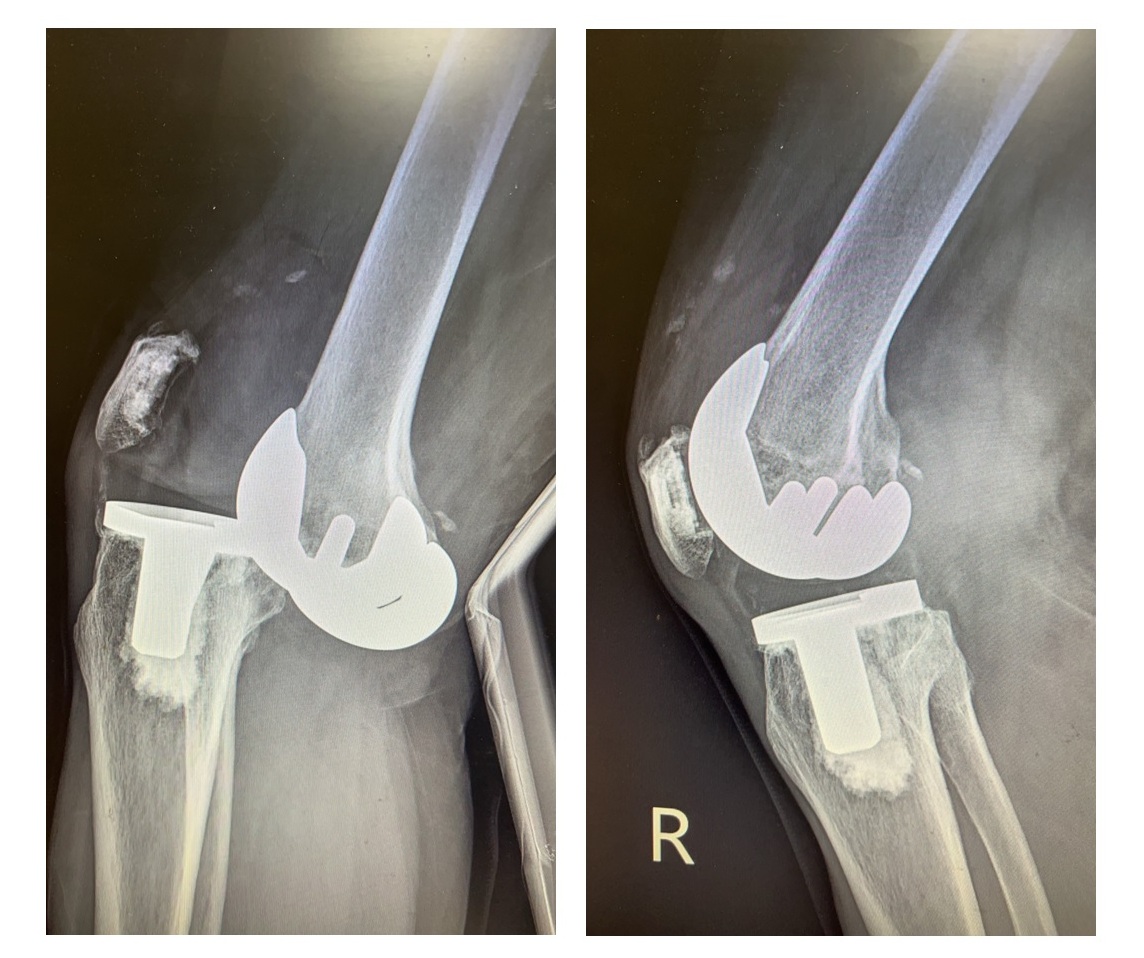

大千綜合醫院骨科醫師容志雄分享近日治療的兩個案例,第一位是93歲的奶奶,20年前曾接受人工膝關節置換手術,使用傳統的人工墊片,近日因跌倒導致整個膝關節骨頭破裂,必須以傳統開刀方式進行治療,用鋼板鋼釘來支撐骨頭,加上病人骨質疏鬆嚴重,另需以石膏副木固定三個月,雖然後續骨頭痊癒也可行動,但她的膝關節彎曲功能卻因此變差。另一位病人是71歲的女士,不小心踩到地上的青苔滑倒,因為6年前她接受人工膝關節置換手術時,使用的是高貼合度的人工膝關節墊片,因此跌倒後雖然關節脫臼錯位,但骨頭整體沒有大問題,只需在輕微的麻醉下將錯位的關節拉回,並針對膝關節股骨內踝撕裂性骨折進行副木固定,一個月就恢復正常,膝關節功能也不會受影響。

71歲女士使用高貼合度人工墊片,跌倒後僅關節脫臼,骨頭無問題(如左圖),將關節拉回後並無大礙(如右圖)。